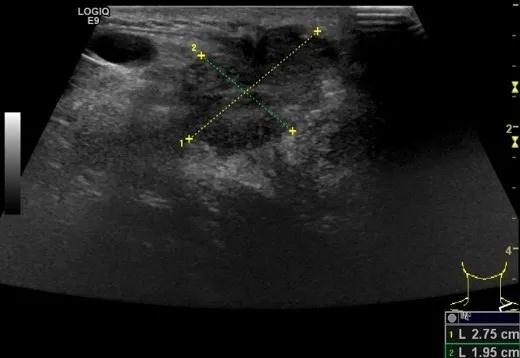

随后,徐栋教授进一步分享了五个临床实战病例,带来了更直观的热消融治疗经验。第一个病例是62岁肺癌患者,术后1年余发现双侧锁骨上淋巴结复发,侵犯神经,存在静脉回流、淋巴回流障碍,肿胀、疼痛非常明显。影像显示患者淋巴结边界不清、形态不规则,存在浸润,血流强化增强。由于患者在系统治疗后进展,且主要目的缓解症状、减瘤。局麻下行热消融术,从后向前逐层消融,热消融之后超声造影即刻评估显示完全充盈缺损,完全覆盖病灶。

(病例1图例)